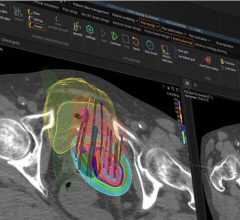

September 20, 2022 — UC San Diego Health is the first hospital system in San Diego to offer a new, highly targeted and ...